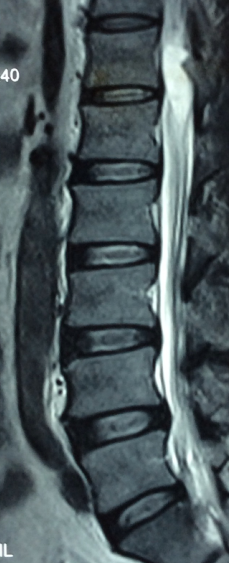

主诉:左下肢麻痛半年,加重伴乏力2周。 病史:患者半年前无明显诱因出现左下肢麻痛,腰部疼痛不明显,久站后有酸胀感。加重伴乏力2周;患者目前无二便失常。患者一般情况尚可。

体查:脊柱无明显畸形侧凸。各棘突及棘旁无明显压痛;左下肢肌力较右侧稍减弱,余四肢肌张力、感觉等无明显异常;双侧膝反射、踝反射无明显异常。病理征未引出。 辅助检查:三大常规、血生化检查未见明显异常,主要脊柱影像学检查如下,请参阅。

诊断:T12-L1椎管内肿物 治疗:患者入院后尽快完善相关检查,请神经外科会诊。经治疗组讨论,拟行“T12-L1椎管内肿物切除+钉棒内固定术”。

讨论:患者椎管内肿物,从影像学表现上看,主要考虑神经鞘瘤,但确诊需依靠手术的病理,同时根据患者的病理情况决定下一步治疗。